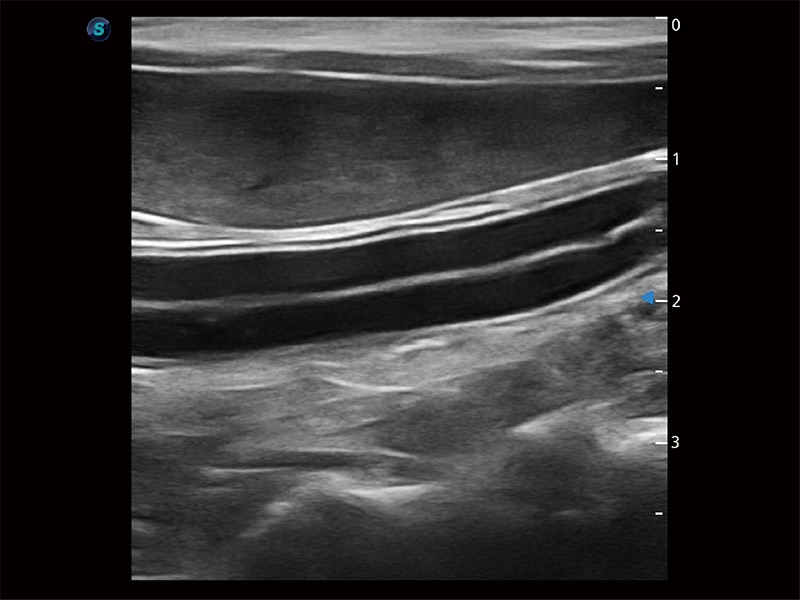

为精细结构及组织边缘提供高清晰度的图像和更大的成像视野。帮助减轻医生的用眼疲劳,快速精准获得测量的数据。

ProPet 80 全新的动物超声智能软件和丰富的探头群,为动物医生提供了高清晰度和精细分辨率的图像,无论在宠物、马科、畜牧还是实验室动物等应用中都可以轻松应对,为您的日常工作带来满意的体验。